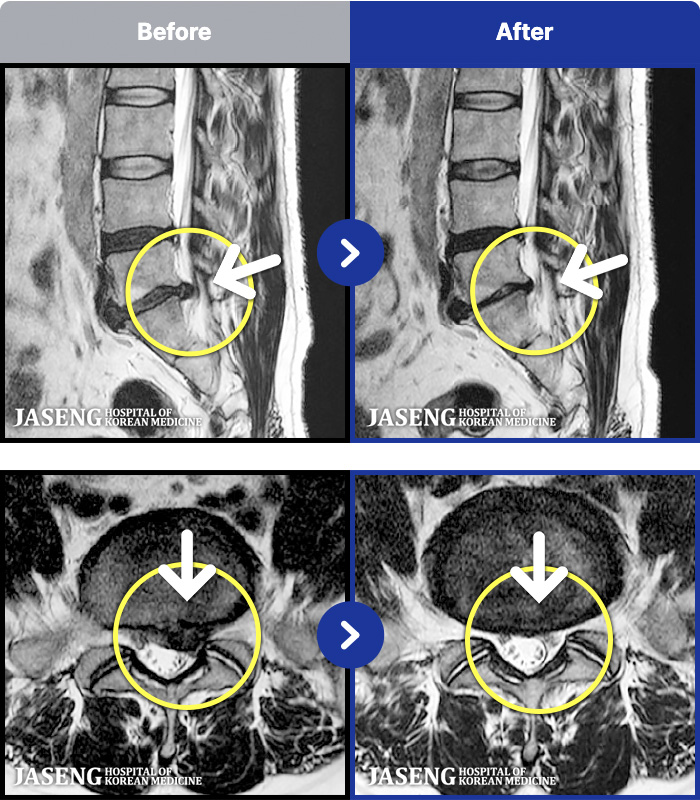

MRI ġ

1,299 MRI ũ ʸ Ȯϼ.